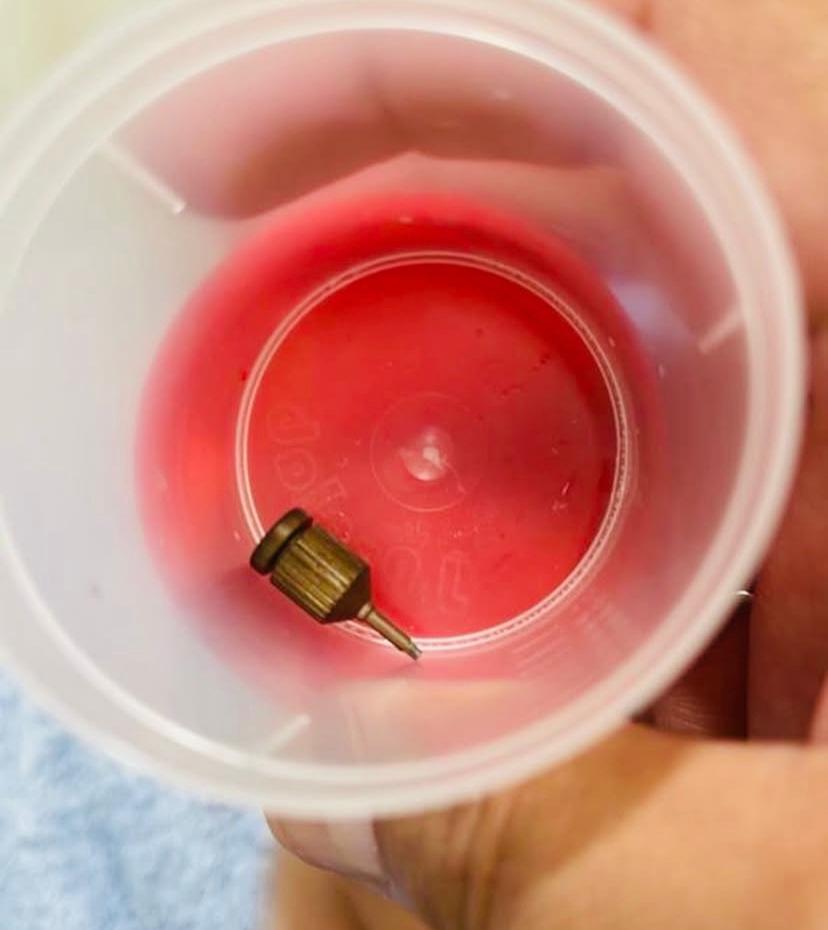

Segundo nota da Coluna Repórter 70, de O Liberal, o objeto foi identificado por acaso, durante exames de imagem realizados no Hospital Albert Einstein, em São Paulo, motivados por dores persistentes na coluna. Após a detecção do corpo estranho — descrito como um pino metálico pontiagudo — os médicos paulistas recomendaram uma cirurgia de urgência para retirá-lo, evitando riscos maiores à saúde da paciente.

“Passei por algo que nunca imaginei viver. Essa peça que aparece na foto foi engolida durante um procedimento odontológico. Avisei, pedi ajuda, e mesmo assim fui ignorada. Só descobri depois que era uma ferramenta pontuda que percorreu meu corpo e precisou ser retirada com cirurgia.”

VEJA FOTOS: